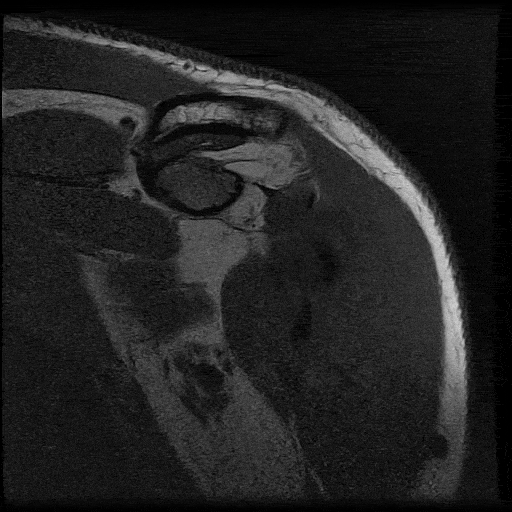

From front to back. This is my left shoulder, so it's as if I'm facing you directly.